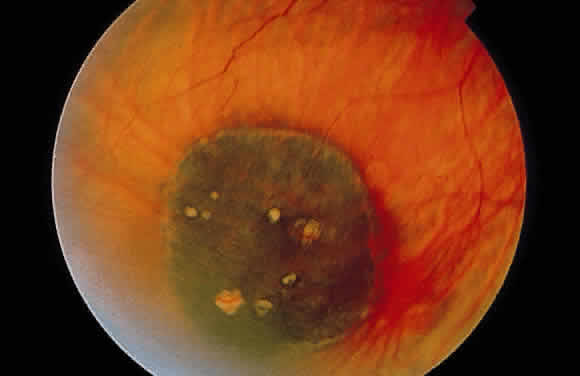

Retinochoroidal colobomas are glistening white or yellow defects with distinct borders that occur inferior or inferonasal to the optic disc (Fig. 12). They may extend up to and involve the optic disc (Fig. 13), or they may be seen as isolated chorioretinal defects. The margins of the coloboma often are pigmented, and the defect is filled with abnormal retinal tissue. Anteriorly, the defect can extend as far as the iris and produce an inferonasal gap (Fig. 14). These anomalies may occur in otherwise normal persons or in association with chromosomal abnormalities or multisystem diseases, such as trisomy 13, the Aicardi syndrome, Goldenhar's syndrome, and the CHARGE association.148,152,153 Occasionally, autosomal dominant or recessive inheritance patterns are found, but often none are evident.152 In families with autosomal dominant inheritance, variable expression of the genetic trait makes genetic counseling difficult.154

Fig. 13. Retinochoroidal coloboma involving the optic disc and inferonasal fundus. The borders of the abnormality are nonpigmented, and the defect appears to be filled with fibroglial tissue.

Embryologically, retinochoroidal colobomas arise from failure of the embryonic fissure to close. Consequently, the inner and outer layers of the optic cup are abnormal in this region. The inner layer (sensory retina) usually is present as a membrane of undifferentiated retina that may have blood vessels going through it (see Figs. 12 and 13). The outer layer (RPE) is absent, and since the choroid is dependent on the RPE for its development, it also is lacking.